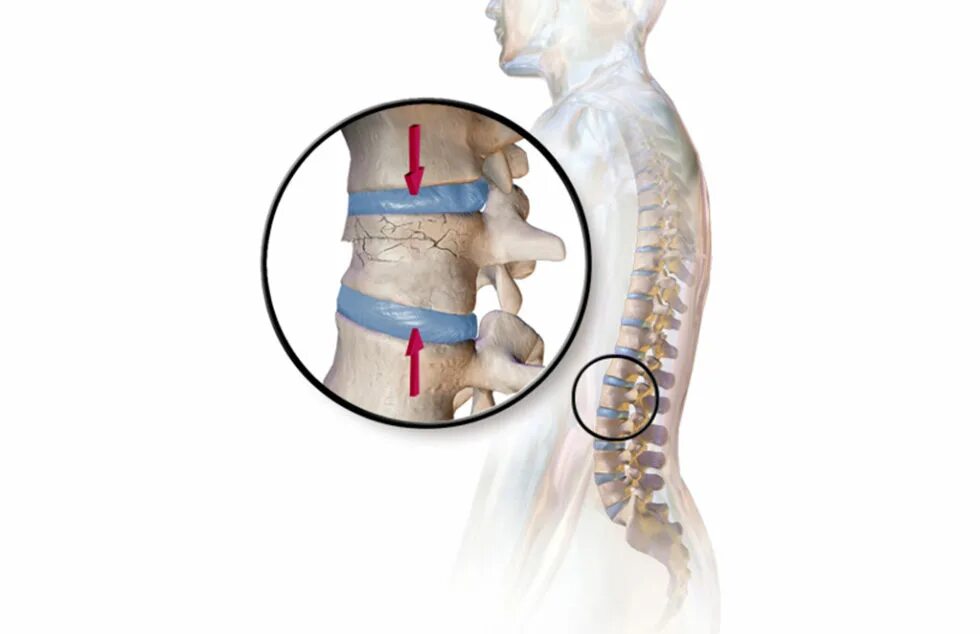

Компрессионный 4 позвонка